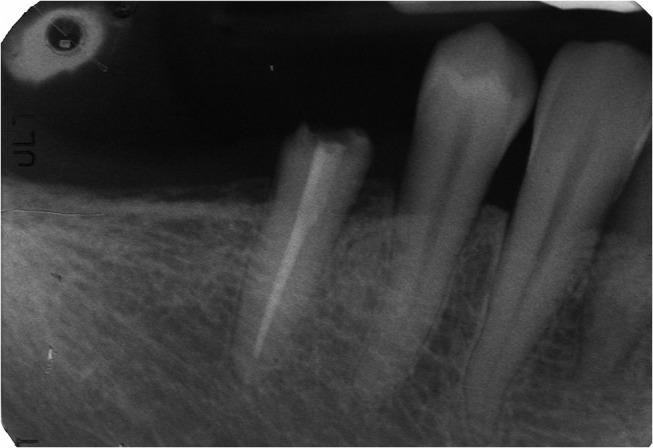

In the reported case an intraoral scan was used to mill a post and core restoration on an endodontically treated inferior premolar; this operative protocol was based on previous in vitro experiments that confirmed the ability of 3shape Trios scanner to read post-space up to 9 mm in depth.

在本报告病例中,使用口内扫描仪为一颗根管治疗后的下颌前磨牙制作桩核修复体;该手术方案基于先前的体外实验,该实验证实了3shape Trios扫描仪能够读取深度达9毫米的桩道空间。